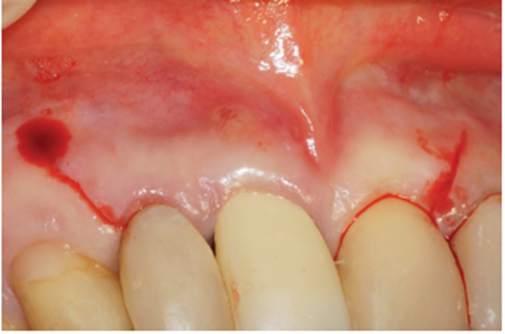

O procedimento cirúrgico foi iniciado através de uma anestesia infiltrativa com articaína 4%. Foram realizadas incisões relaxantes (Figura 4) para expor o leito cirúrgico e, consequentemente, a lesão periapical (Figura 5). Após o deslocamento do retalho, foi realizada a exodontia de forma atraumática (Figura 6) e na sequência, foi feita a curetagem do alvéolo removendo todo o tecido de granulação (Figura 7). Uma vez realizada a toalete do leito cirúrgico (Figuras 8 e 9), o implante Cone Morse Due Cone de 3.5 X 13 mm (Implacil De Bortoli) foi instalado seguindo o melhor posicionamento dentro do rebordo residual, conforme planejado (Figuras 10 e 11). Em sequência, foi realizada a instalação do Cover Screw (Figura 12) e o preenchimento do defeito ósseo com biomaterial (Bio-Oss 0,25), conforme figuras 13 e 14). O fechamento foi realizado com membrana de PTFE-d (Cytoplast TXT–200, Osteogenics – Lubbock TX, EUA), customizada para ser adaptada sobre o defeito ósseo, estendendo-se de 3 a 5 mm da margem do defeito ósseo e intencionalmente exposta (Figura 15). A sutura foi realizada com fio de PTFE (Cytoplast), como podemos observar na figura 16, e instalado um provisório adesivo na região (Figura 17).